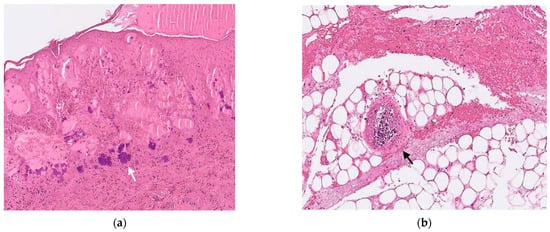

At the PICU, ceftazidime was shifted to cefepime, amikacin, and teicoplanin. Cultures of skin lesions yielded MSSA. Incisional biopsy of necrotic bullae revealed aggregates of Gram-positive cocci (GPC) at the subepidermal area (Figure 2a) and necrotic vasculitis without perivascular bacterial invasion (Figure 2b). Cultures of blood, urine, and cerebrospinal fluid were all sterile. Culture of stool did not yield Pseudomonas aeruginosa. His consciousness and activity improved gradually, and his skin lesions began to crust, desquamate, and heal. Antibiotics were then de-escalated to monotherapy with cefepime. On hospital day 11, laboratory studies revealed a white blood cell count of 6100/mm3, an absolute neutrophil count of 488/mm3, and a C-reactive protein level of 16 mg/L. The flow charts of presenting symptoms, laboratory data, and treatment courses in the hospital days are presented in Figure 3. An immunodeficiency study of T cell, B cell, lymphocyte proliferation, chemotaxis, and macrophage was unremarkable. A whole exome gene survey, especially the ELANE gene, for the detection of neutropenia showed a negative result. After completing 2 weeks of cefepime, he was discharged home with oral cephalexin.

In our case, the organism was grown from culture of the skin lesion but not in blood cultures. Of the seven reported cases, there were only two cases with positive blood culture, but GPC were pathologically noted within the dermis in most cases. In our case, we clearly demonstrated aggregates of GPC at the subepidermal area of the skin lesion and necrotic vasculitis but without perivascular bacterial invasion into the vessels.

Figure 2. The pathologic images (Gram stain, ×200) of the incisional biopsy of the papulonodular skin lesion reveal (a) aggregates of Gram-positive cocci (white arrow) at subepidermal area and (b) necrotic vasculitis (black arrow) without perivascular bacterial invasion (Hematoxylin and Eosin stain, ×200).